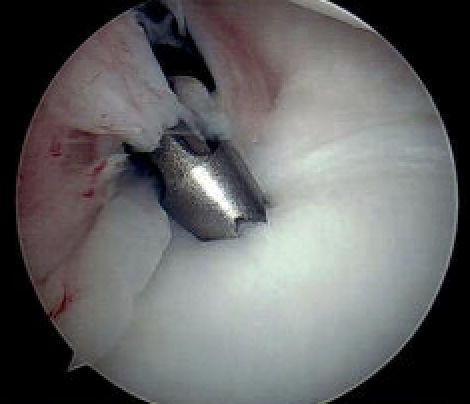

Arthroscopic capsular plication

Technique

Anterior capsular plication +/- rotator interval closure

- option 1: Suture plicate capsule to labrum

- option 2: Anchors in glenoid and use to plicate capsule to labrum